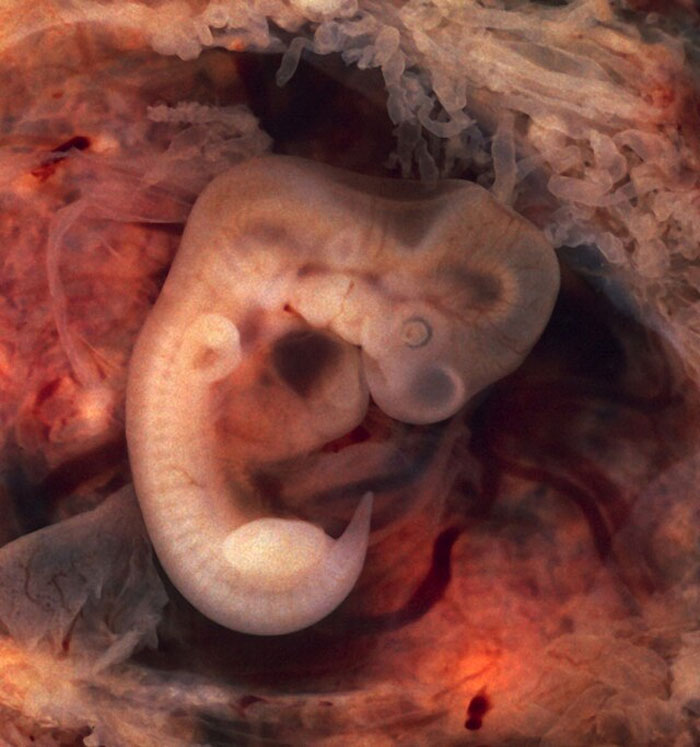

Not an autopsy per se, but back when I was working as a lab assistant, we received something that both the doctor in charge and I were stumped by. After many attempts at understanding what it was and cutting different sections, I finally realized it was a pretty malformed embryo. The tiny little head still breaks my heart. I’ve seen a lot of weird anomalies and held different organs in my hands, but that was a full human that could have never made it to life. It hits you in a different way.

Image credits: Lady-Dopamine